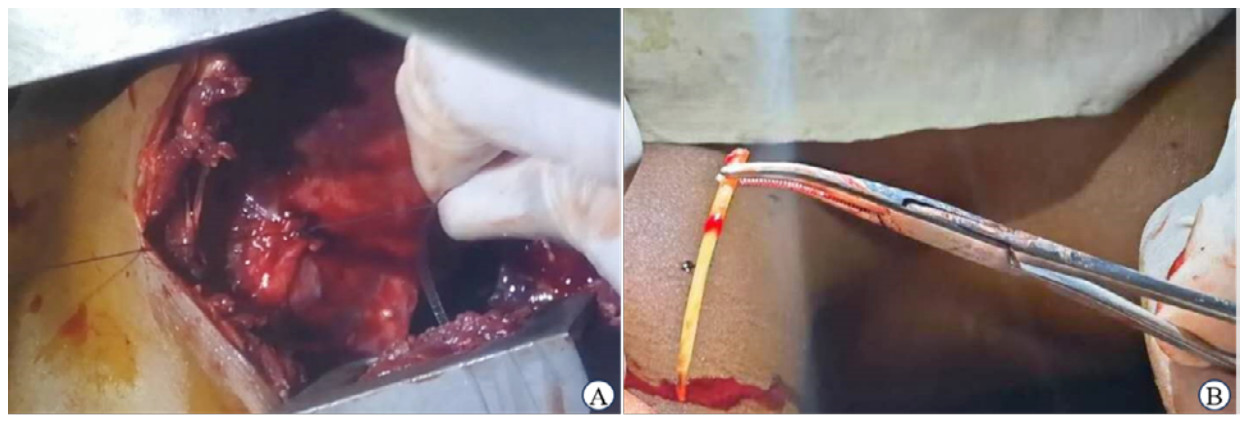

根据患者病史及辅助检查,考虑外伤后左心室异物遗留,左下肺感染、肝硬化伴功能不全、贫血和血小板减低,合并多种传染性疾病和凝血功能异常。入院当天开始给予头孢曲松钠2 g抗感染,1次/d静脉滴注,患者入院后体温正常,本地区无法开展成分输血,治疗5 d后查体睑结膜发白,输新鲜全血400 mL纠正贫血、改善凝血功能,第6天复查血红蛋白111 g/L、血小板74×109/L,在脉搏氧饱和度和袖带血压监测下采用保留自主呼吸非气管插管硬膜外麻醉实施左心室异物取出术,左侧第5肋间开胸,探查见左侧胸腔少量淡黄色积液,左肺上叶下舌段和下叶基底段肺组织与心包黏连,膈肌侧叶间裂可见一鸡蛋大小的椭圆形囊性包块,打开后约50 mL白色稀薄脓液流出,异味不明显,彻底清除囊壁,钝性分离黏连,近心尖处左心室前壁心包与心脏紧密黏连,局部明显增厚,使用手术刀片轻刮后触及明显硬质异物,使用2-0 Nylon线以异物为中心,直径约1.5 cm带黏连的心包缝圆形荷包,深度到心室肌层,使用中弯钳夹紧异物并拔出,收紧荷包线打结(图 2A)。异物为仙人掌刺,中间段直径约2 mm,长约4 cm(图 2B);剥脱并切除部分与左心室前壁黏连的心包,检查无活动性出血后使用碘伏盐水冲洗胸腔后于腋中线第7肋间放置胸腔引流管,关胸术毕。术中患者轻碰后出现右侧鼻孔出血,纱布填塞止血。手术时长1 h,患者术后继续使用头孢曲松抗感染治疗,用法同术前。术后24 h引流淡血性液体450 mL,输新鲜全血400 mL;术后第7天拔除引流管,双肺呼吸音清,术后无发热,四肢活动无异常,停药观察,术后第11天出院,生命体征平稳,无不适主诉,嘱出院后戒酒、低盐饮食、当地疾控部门复查传染病。出院后2个月和6个月门诊复查恢复良好,复检确诊人体免疫缺陷病毒和乙型肝炎病毒感染,未行特殊治疗,血压正常范围。

| 注:A为将仙人掌刺从左心室前壁拔出后收紧带心包组织的荷包缝线止血,心包增厚并局部黏连;B为从左室壁拔出的仙人掌刺,中间直径约2 mm,长约4 cm 图 2 患者手术资料 |

患者开胸探查可见急慢性混合感染表现,异物尾端位于左心室前壁近心尖处,与心包紧密黏连,先打开周围心包观察,判断冠脉与异物的位置,距离较远时采取带垫片以异物为中心的荷包缝合,深度不穿透心室肌为宜;而距离冠状动脉主干或二级分支较近时可采用带垫片跨冠脉水平褥式缝合,异物位于垫片之间,进针处距冠脉至少0.5 cm,深度须达肌层,避免打结后冠脉牵拉扭曲造成心肌梗死,二级以下分支损伤较少出现严重并发症[14]。该患者异物距离冠脉远,直接利用黏连的心包作为垫片缝合荷包,拔出异物后打结,无活动性出血,并将左心室前壁黏连疏松的心包分离切除,防止后期形成缩窄性心包炎影响生活质量。此术式虽简单易行,但可能导致术前未发现的异物血栓和赘生物脱落,引起器官栓塞或感染,且不能探查和治疗继发性心内损伤,术后需严密监测和随访,内科继续治疗肝硬化及传染病,预防并发症。